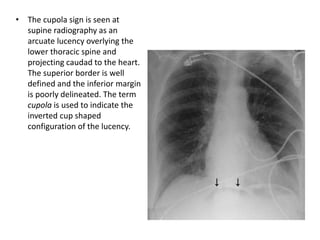

• The cupolasign is seen at supine radiography as an arcuate lucency overlying the lower thoracic spine and projecting caudad to the heart. The superior border is well defined and the inferior margin is poorly delineated. The term cupola is used to indicate the inverted cup shaped configuration of the lucency.

• The cupola sign is seen at

supine radiography as an

arcuate lucency overlying the

lower thoracic spine and

projecting caudad to the heart.

The superior border is well

defined and the inferior margin

is poorly delineated. The term

cupola is used to indicate the

inverted cup shaped

configuration of the lucency.